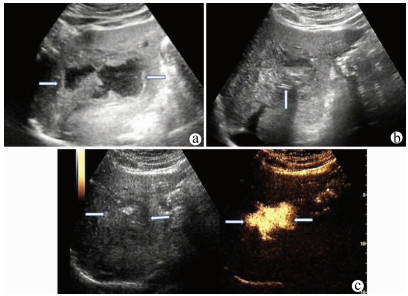

A case of subcapsular hepatic hematoma after endoscopic retrograde cholangiopancreatography

Yihui LUO

2021, 37(8): 1914-1915. DOI: 10.3969/j.issn.1001-5256.2021.08.035

Abstract(754) HTML (247) PDF (1901KB)(48)

Abstract: